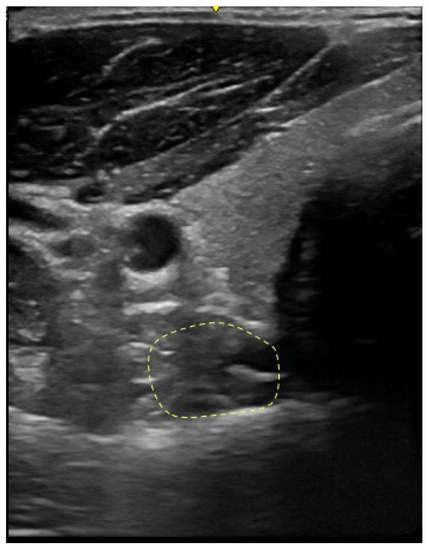

2.3.3. Morphological Characteristics of Deep Neck Muscles